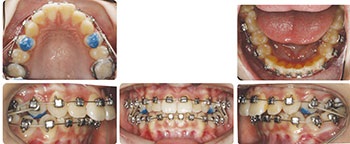

Regarding her upper incisors, in non-extraction cases that show significant crowding or proclination, I will often flip/invert the four upper incisor brackets to induce a reversed/negative prescription torque on those teeth. It is a great technique that has been popularized by Dr. Tom Pitts. In this case, I chose not to use this technique. I felt that, if she complied with the elastics and headgear combo, there would be a more than sufficient distalizing force on the maxillary dentition to retract and normalize the upper incisor A-P position and inclination. If she did not, I still had extractions or an upper incisor bracket flipping in my back pocket for a mid-treatment course correction if necessary.

Most importantly, there would also be an important vertical component to this chosen plan. With Jolie’s cooperation, there would always be an active force of extrusion on the posterior teeth to support our goal of increasing vertical. While Class II elastics were worn during the day, there would be an extrusive force on the lower first molars. When the cervical pull headgear was worn during the night, there would be an extrusive force on the upper first molars.

In addition to their eruptive effects that benefit increasing vertical, cervical pull headgear and Class II elastics both mechanically favor tipping of the occlusal plane in a clockwise manner. This, in combination with an exaggerated “SAP” bracket positioning (a la Dr. Tom Pitts) that I opted for, would attempt to increase her deficient VID and her flat SA.

‘Short-Face’ Patients—Part 3

Fig. 3

Results

Jolie’s case finished in 26 months total (Figs. 3–9). On a side note, I think it is also important to note that, in cases with vertical gain via posterior extrusion, I am typically in no hurry to finish treatment quickly. There is value in letting them sit for a few extra months in active retention. With intentional education and motivation provided to her during treatment, Jolie understood what was possible regarding her facial and smile improvement with our chosen treatment. That understanding fortunately translated to an engaged patient and great cooperation on her end.